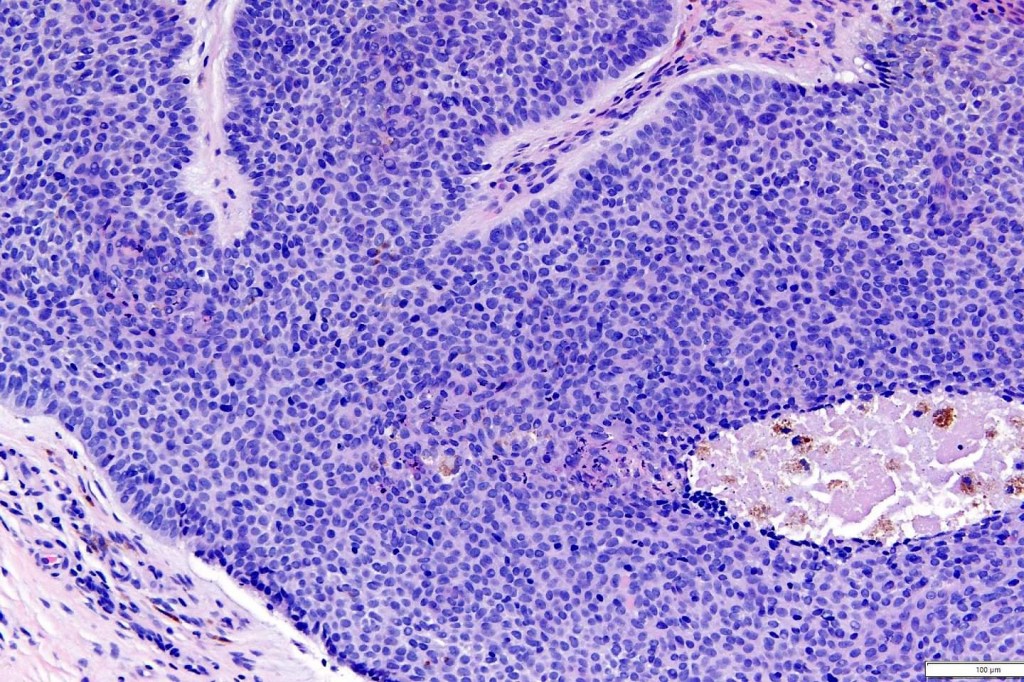

•No pleomorphism

•No mitoses

•CD20+ve Merkel cells

•Outermost layer bcl-2 expression (compare with BCC)

•Low Ki67 expression (compare with marked expression in BCC)